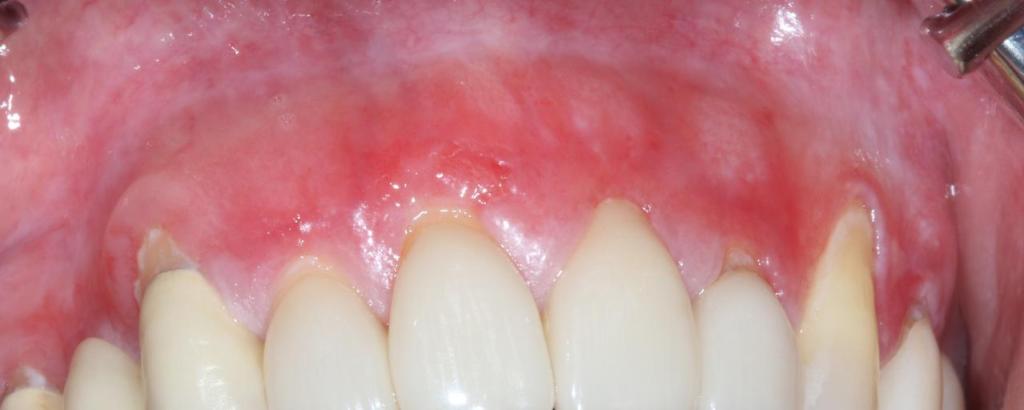

A new study has been initiated at the University of Gothenburg to study the effects on oral health from using nicotine pouches. The university has released a statement detailing that the study is being initiated because a number of dental patients referrals from dental clinics to the University. These patients have gum damage that differs from what is commonly seen in users of traditional tobacco-based snus. This statement has been widely reported by Swedish news media.

A pilot study with 23 Swedish dentists who were daily pouch users of either tobacco snus or nicotine pouches (referred to as “white snus” in the University of Gothenburg statement , several of which had similar gum issues to those documented by Dr Gale including irritated or inflamed gums, snus lesions and receding gums. In our test the occurrence and severity of gum irritation and snus lesions was reduced significantly when users switched to using only Stingfree pouches for 5 weeks. Stingfree pouches have the same type of contents as ordinary pouches but the pouch itself has a protective layer called PROTEX that prevents direct contact between the pouch contents and the users’ gums.